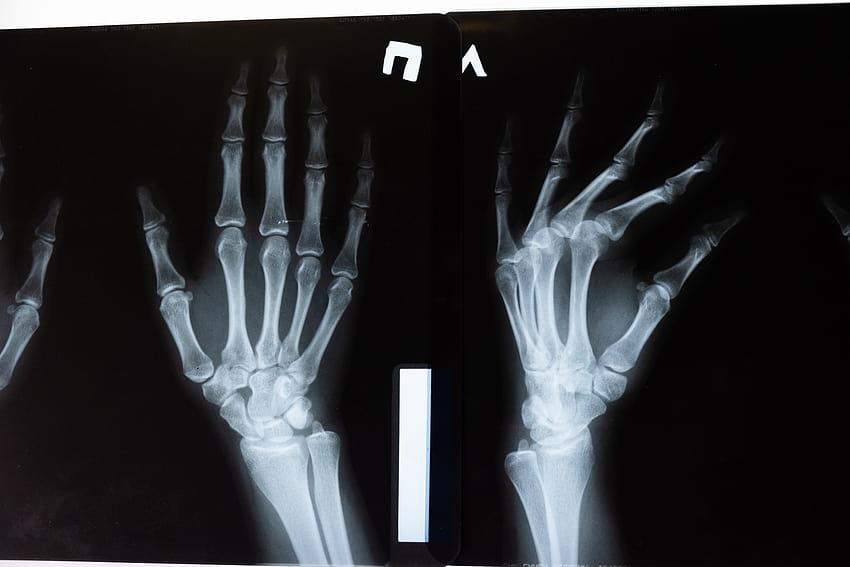

Напомним, что несчастный случай произошел в Коврове во Владимирской области. 16-летний юноша колол дрова и случайно отрубил себе кисть правой руки.

Пострадавшего оперативно доставили в Нижний Новгород в Университетскую клинику Приволжского исследовательского университета. В тот же день врачи Института травматологии и ортопедии ПИМУ провели операцию по реплантации конечности.

Сейчас юноша до сих пор находится в больнице. Ему предстоит еще несколько операций, так как необходимо восстанавливать функциональность кисти. Для этого потребуется вмешательство нейрохирургов.

Врачи назвали его состояние удовлетворительным. Сам пациент не отчаивается и верит в лучшее.